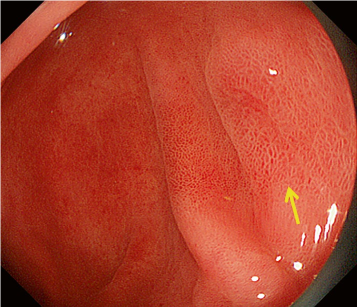

The working group members carried out a systematic review of the English literature to determine widely accepted diagnostic systems. Consequently, the best-accepted diagnostic system was proven to be the VS classification system. Based on this system, MESDA-G was constructed using an evidence-based approach (. Figs. 3, 4, 5, and 6) [2]. First, lesions suspicious for EGC should be detected by careful inspection using conventional white-light endoscopy. Subsequently, magnified observations should be performed. Owing to the high sensitivity of the demarcation line [8], if it is absent, the suspicious lesion is diagnosed as noncancerous (. Fig. 4a, b). However, if the demarcation line is present, further assessment is required to determine the presence of an irregular MV or MS pattern. If an irregular MV and/or MS pattern is detected, the suspicious lesion is diagnosed as cancerous (. Fig. 6a, b) [1, 5, 6, 8]. If both the irregular MV and MS patterns are absent, the tumor is diagnosed as noncancerous (. Fig. 5a, b) [1, 5, 6, 8].